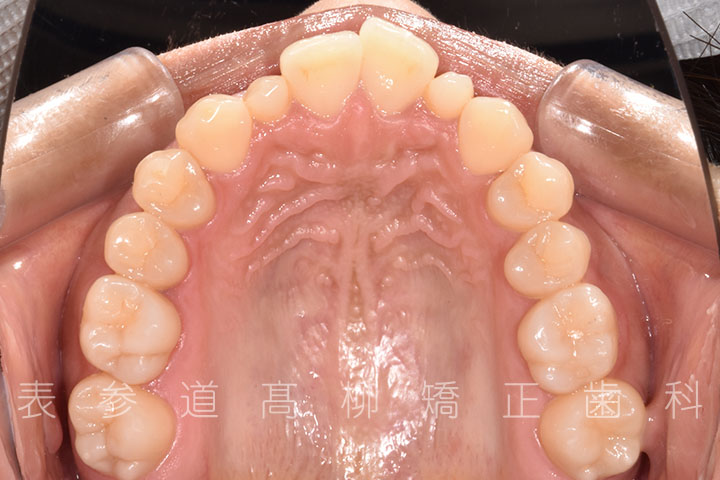

• 補綴治療終了

・矯正治療終了後 加部歯科医院(https://kabe-dent.net) にて2⏊2補綴処置を行った

・2⏊2矮小歯(先天的に形態が小さい歯)